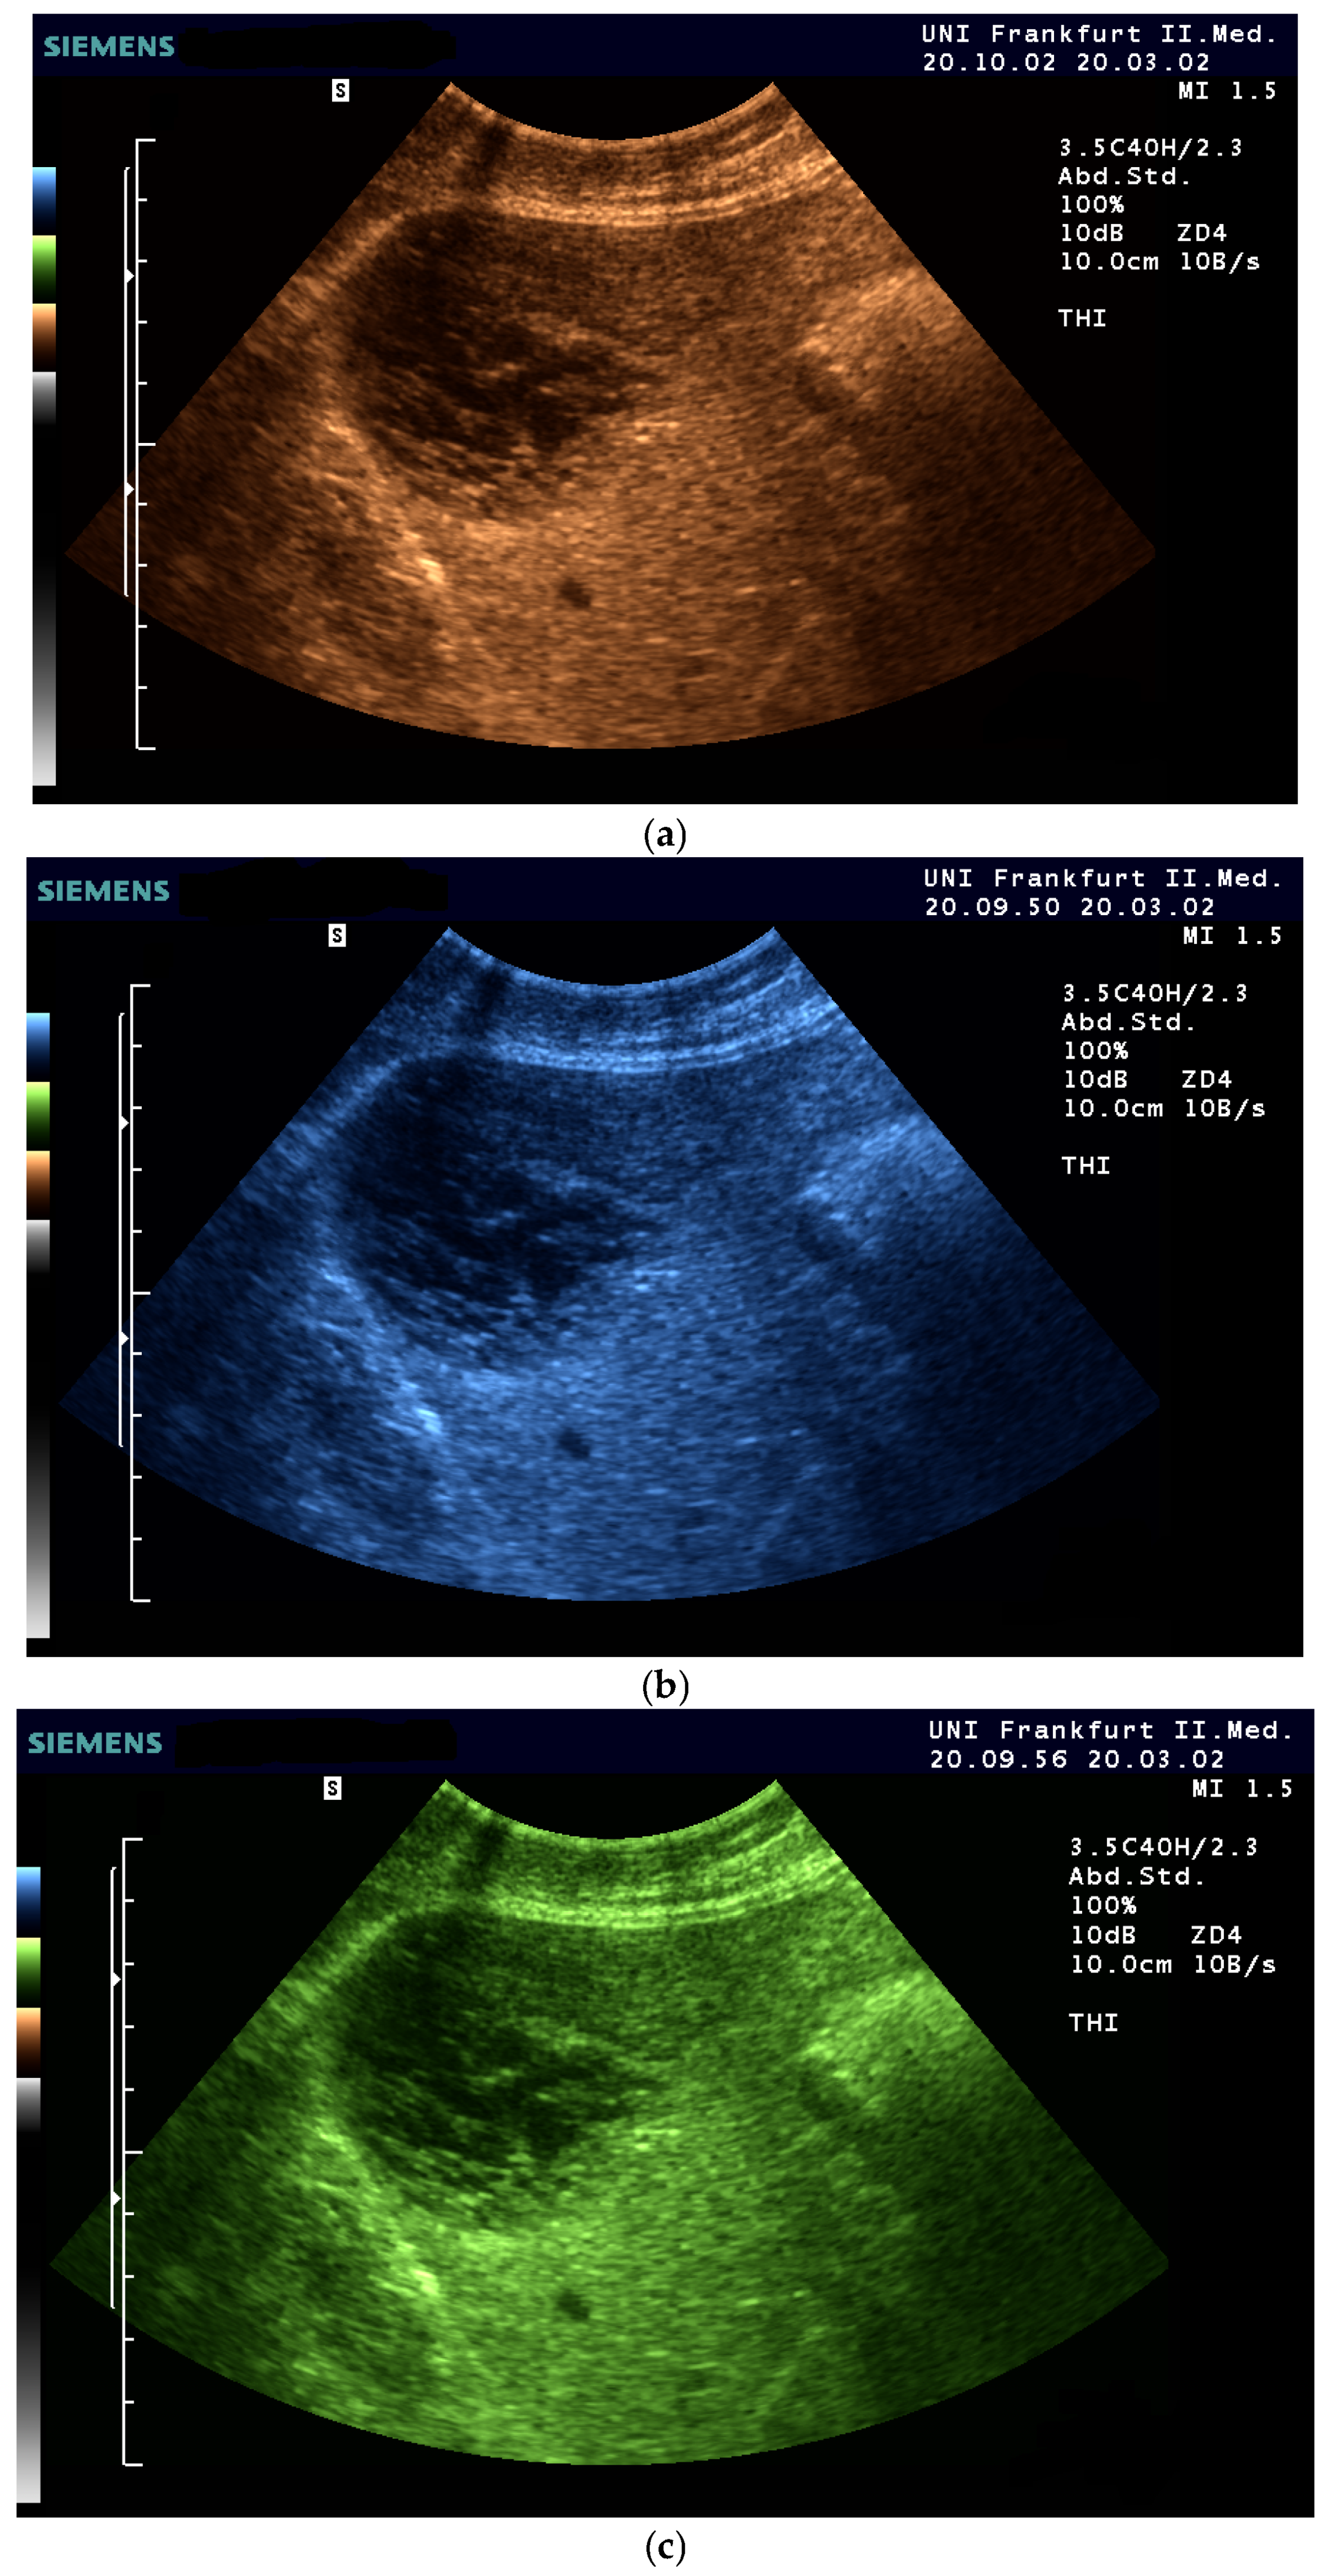

- The combination with speckle filters available in all high-end devices, similar to the low-pass filters used by Bleck et al. (1994) for tissue visualization [5], also yields significantly improved visualization results (Figure 5, Figure 6 and Figure 7). In principle, applications with new visualized texture analyses, such as random field models, are also conceivable [76,77].

- Fischer, T.; Filimonow, S.; Taupitz, M.; Petersein, J.; Beyersdorff, D.; Bollow, M.; Hamm, B. [Image quality and detection of pathology by ultrasound: Comparison of B-mode ultrasound with photopic imaging and tissue harmonic imaging alone and in combination]. Rofo 2002, 174, 1313–1317. [Google Scholar] [CrossRef] [PubMed]

- Merkel, D.; Brinkmann, E.; Kammer, J.C.; Kohler, M.; Wiens, D.; Derwahl, K.M. Comparison Between Various Color Spectra and Conventional Grayscale Imaging for Detection of Parenchymal Liver Lesions With B-Mode Sonography. J. Ultrasound Med. Off. J. Am. Inst. Ultrasound Med. 2015, 34, 1529–1534. [Google Scholar] [CrossRef]